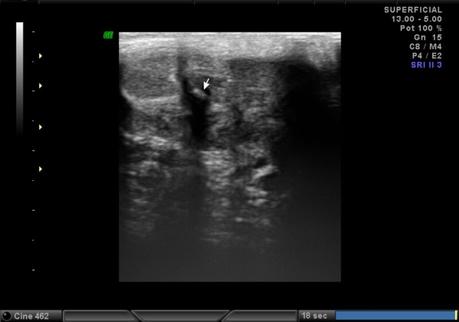

A nivel de base del pené, entre los cuerpos cavernoso y esponjoso en su porción central se observa la presencia de calcificación, que mide 2.2 mm. En tercio distal del pené, a nivel de cuerpos cavernosos con presencia de calcificación que mide 1.8 mm.

A NIVEL DE BASE Y TERCIO DISTAL DEL PENÉ, EN CUERPOS CAVERNOSOS CON PLACAS A RELACIÓN A ENFERMEDAD PEYRONIE.